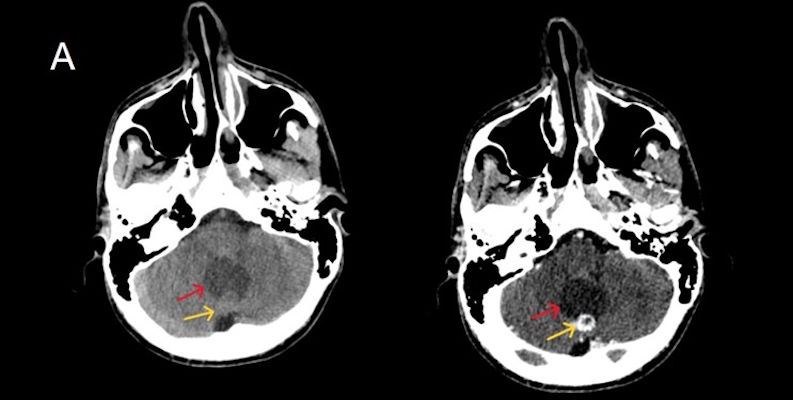

- A) Beyin BT incelemede; posterior fossada hipodens, düzgün sınırlı kistle beraber (oklar), posteriorunda 8 mm boyutunda, iyi sınırlı, kontrastsız BT’de parankim ile izodens, postkontrast görüntülerde yoğun kontrast tutulumu gösteren mural nodül komponenti (oklar) gözlenmektedir.

- BT’de tipik olarak iyi sınırlı, hipodens kistik bir lezyon ve içinde belirgin şekilde kontrastlanan mural nodül izlenir.

- Kalsifikasyon: Hemanjioblastomlarda kalsifikasyon çok nadirdir (oligodendrogliom ve ependimomlardan ayırt edici bir özellik).